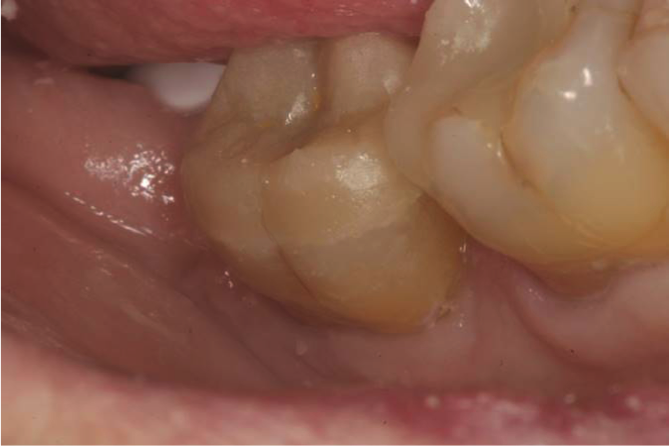

Fig. 3  In this alternative technique to selective etching, “active application” of a universal adhesive to both the enamel and dentin increases the rate of solvent evaporation and facilitates fusion of the monomer into the smear layer.

Figure 3

An alternative to the standard selective-etch technique is to apply the universal adhesive to both the enamel and dentin after the tooth is prepared but before the impression or scan. Active application of the adhesive (Figure 3) has a number of advantages. Agitation with a microbrush continuously keeps the fresh self-etchant in contact with the dentin, increases the rate of solvent evaporation, and facilitates fusion of the monomer into the smear layer. Manual pressure of the microbrush also compresses the collagen network. When the agitation is stopped and the pressure is relieved, the compressed collagen expands like a sponge and draws in the surrounding adhesive.20 After actively applying the 10-MDP-based adhesive, it is air-thinned to remove the remaining solvent and light-cured.